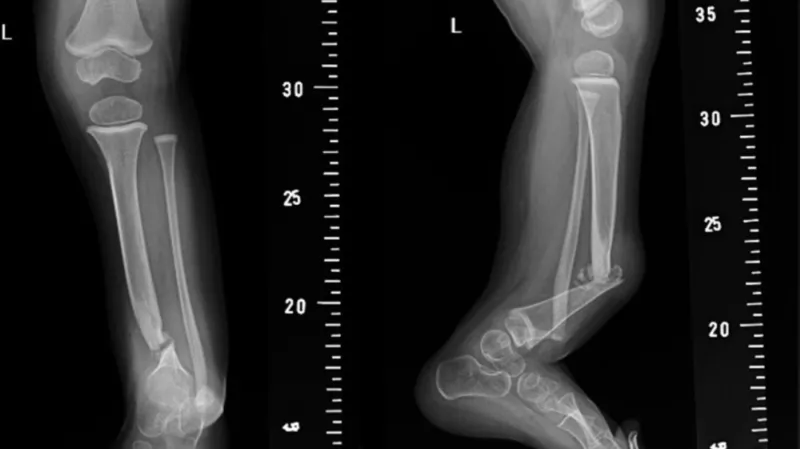

V České republice přijde na svět jedno až tři děti s pakloubem bérce ročně. Dítě se rodí buď se zlomenou holenní kostí, nebo s deformitou a ke zlomenině dochází až po narození, často ještě v prvním roce života. Pokud se jednou holenní kost zlomí, konzervativní zhojení je prakticky nemožné.

„Zákrok trvá okolo pěti hodin, kdy se zavede kovový implantát do dřeňové dutiny kosti. Ten je v horní části bérce fixován závitem, v dolní drátkem. Tím, že je kovový implantát fixován nad a pod růstovými zónami bérce, kost může růst a implantát víceméně roste s pacientem,“ vysvětlil Karel Urbášek, vedoucí ortoped Kliniky dětské chirurgie, ortopedie a traumatologie FN Brno.

Pro úspěšné spojení holenní a lýtkové kosti je nutné odebrat pacientovi veškerou kost z vnitřku jedné poloviny pánve, ta se v průběhu šesti až dvanácti týdnů po operaci plně obnoví. Metoda umožňuje pacienta operovat už v 18 měsících, dříve používané postupy umožňovaly operaci až ve třech nebo čtyřech letech. Dítě přitom až do operace nemůže samo chodit.